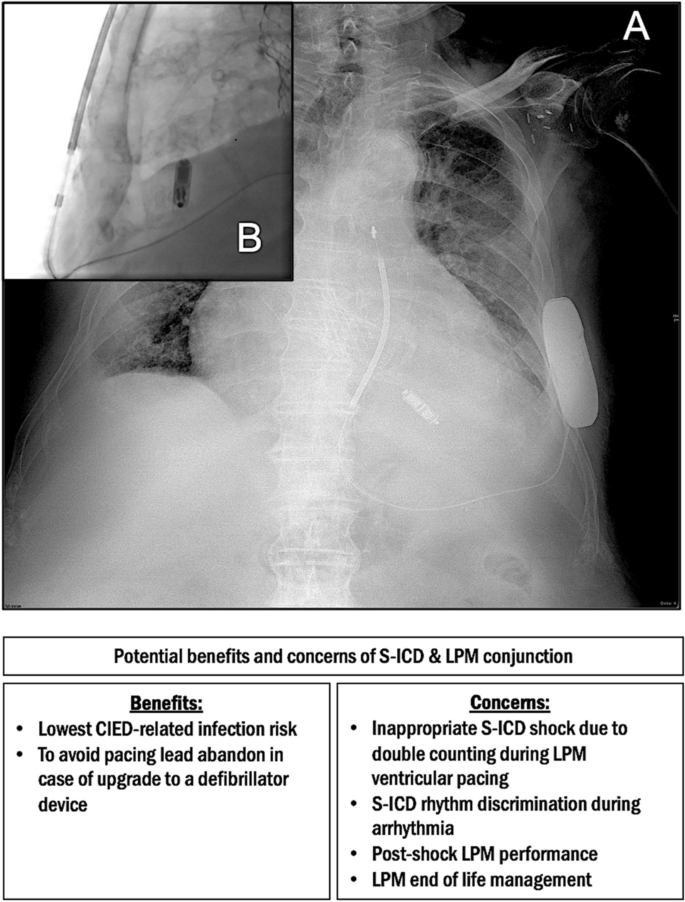

Co-presence of subcutaneous implantable cardioverter-defibrillator and leadless pacemaker in high-risk infection patients: are we out of the woods?